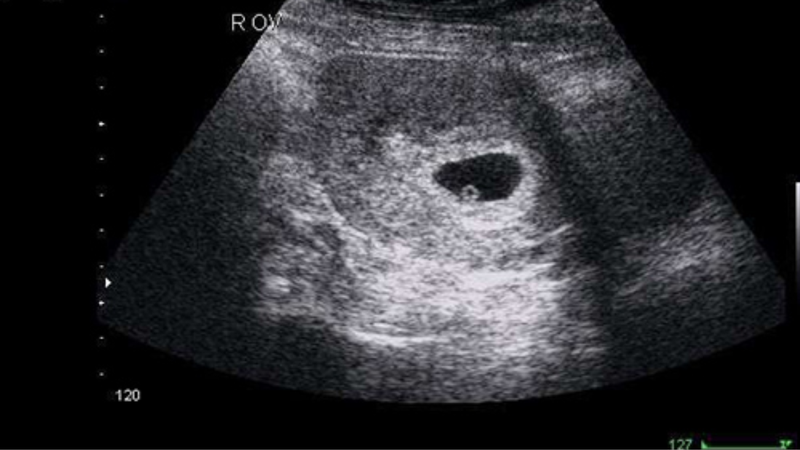

Hình ảnh túi thai 5 tuần tuổi vẫn còn rất nhỏ. Qua siêu âm đầu dò, bác sĩ chỉ có thể nhìn thấy túi thai và túi noãn hoàng (yolksac), rất hiếm khi nhìn thấy phôi thai. Nếu có, phôi thai chỉ ở giai đoạn rất sớm, xuất hiện như những chấm nhỏ bên cạnh túi noãn hoàng.

Khi quan sát hình ảnh túi thai 5 tuần qua siêu âm đầu dò, mẹ có thể thấy một vùng màu đen với một vòng tròn nhỏ bên trong. Vùng đen này chính là túi thai, còn vòng tròn nhỏ màu trắng là túi noãn hoàng.

Túi noãn hoàng có vai trò cung cấp dinh dưỡng cho phôi thai phát triển trong giai đoạn nhau thai chưa hình thành. Từ khoảng tuần thứ 14 đến tuần thứ 20, khi nhau thai đã phát triển hoàn thiện, túi noãn hoàng sẽ dần biến mất.